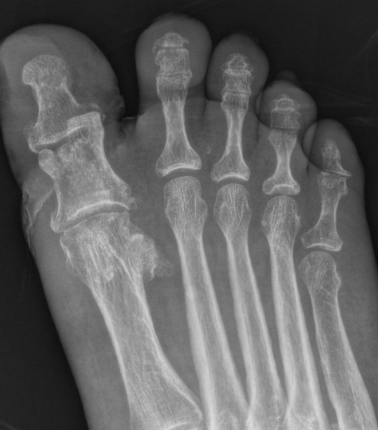

Interphalangeal joint dislocation

Pathology

Hyperdorsiflexion

P1 head dislocates plantar

Fractures

Xray

Blocks to closed reduction

Sesamoid interposition

Open Reduction

Dorsal Approach

- protect dorsal superficial nerve

- divide capsule medial to EHL

Reduce +/- K wire

Surgical approach to interphalangeal joint dislocation